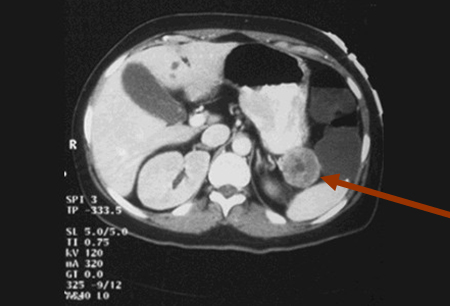

VIPoma

Computed tomography image of VIPoma near the tail of the pancreas

From the collection of Charles J. Yeo, MD; used with permission